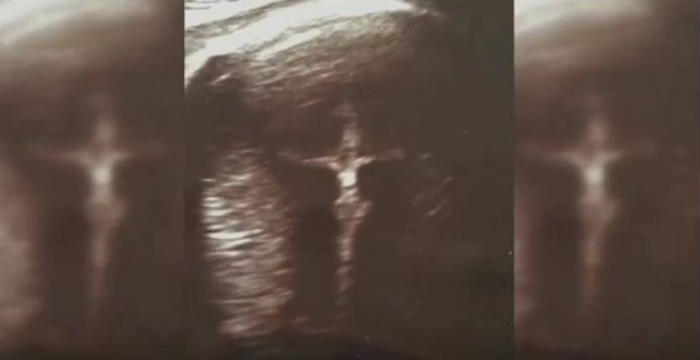

Ένα ανέλπιστο «δώρο ζωής» χάρισε η τεχνολογία σε μία 44χρονη μητέρα με προβλήματα όρασης. Κατάφερε να «δει» το αγέννητο μωρό της, μέσα από την αίσθηση της αφής. Το ...